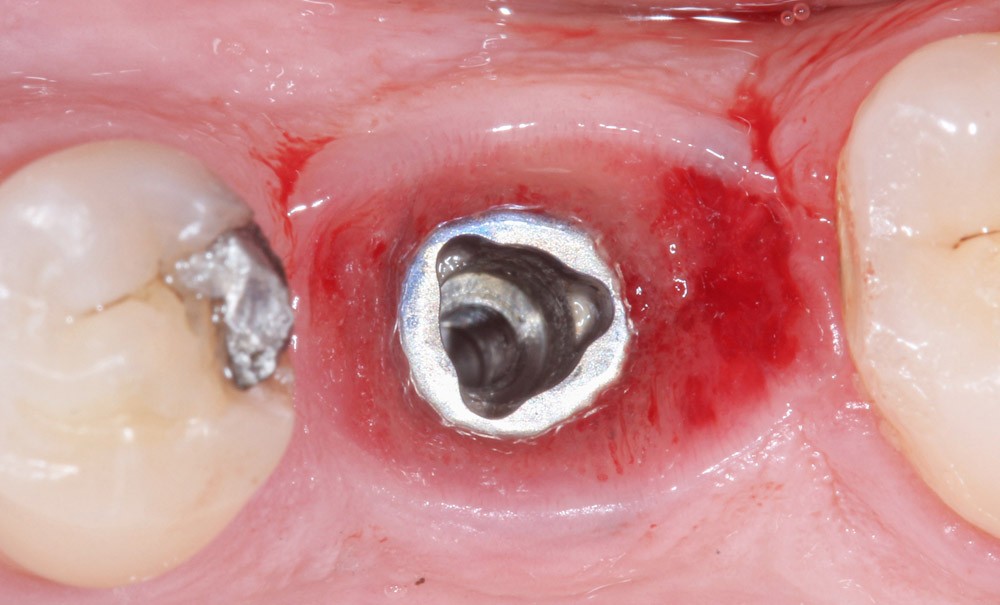

Un patient, sans problème de santé systémique, consulte pour des douleurs chroniques sur une prothèse implanto-portée unitaire. L’implant remplace la seule dent absente de l’arcade mandibulaire, l’édentement est encastré.

La première chose remarquable en bouche est la bonne intégration de la prothèse : l’ensemble est immobile, intact (la prothèse ne présente pas d’éclats de céramique), les points de contacts sont également présents. Un dévissage ou une altération de la restauration n’apparaissent pas comme de possibles causes aux douleurs décrites. Les tissus péri-implantaires sont d’aspect sain, sans saignement, gonflement ni présence de pus.

Un puits de vissage indique que la prothèse est vissée : le ciment n’est a priori pas en cause ici. Le patient a bénéficié, sur certaines dents naturelles, de restauration dento-portées…